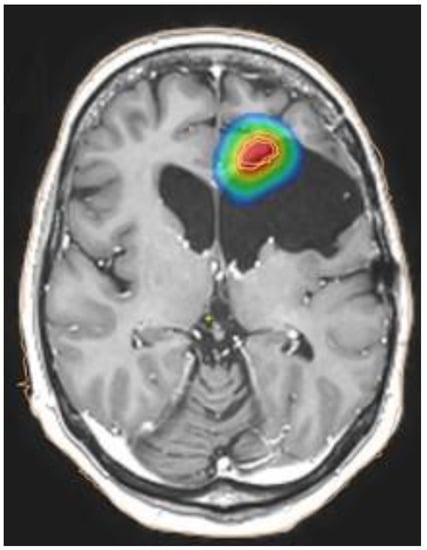

- Miwa, K.; Matsuo, M.; Ogawa, S.; Shinoda, J.; Yokoyama, K.; Yamada, J.; Yano, H.; Iwama, T. Re-irradiation of recurrent glioblastoma multiforme using 11C-methionine PET/CT/MRI image fusion for hypofractionated stereotactic radiotherapy by intensity modulated radiation therapy. Radiat. Oncol. 2014, 9, 181. [Google Scholar] [CrossRef] [Green Version]